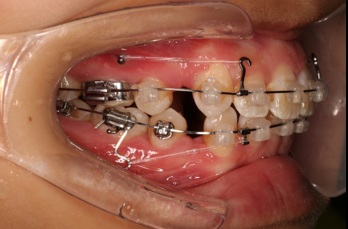

2016.10.31  初戴,0.013cu-niti2017.1.13  上颌加TPA,U56间斜形植入韩国庆北1312-08种植钉,上下0.16cu-niti

2017.02.16  上下0.014*25 cu-niti,50g 拉尖牙远中

2017.04.28

2017.04.28  上0.016*25ss 13、23近远中约5度 v形曲,下0.017*25ss